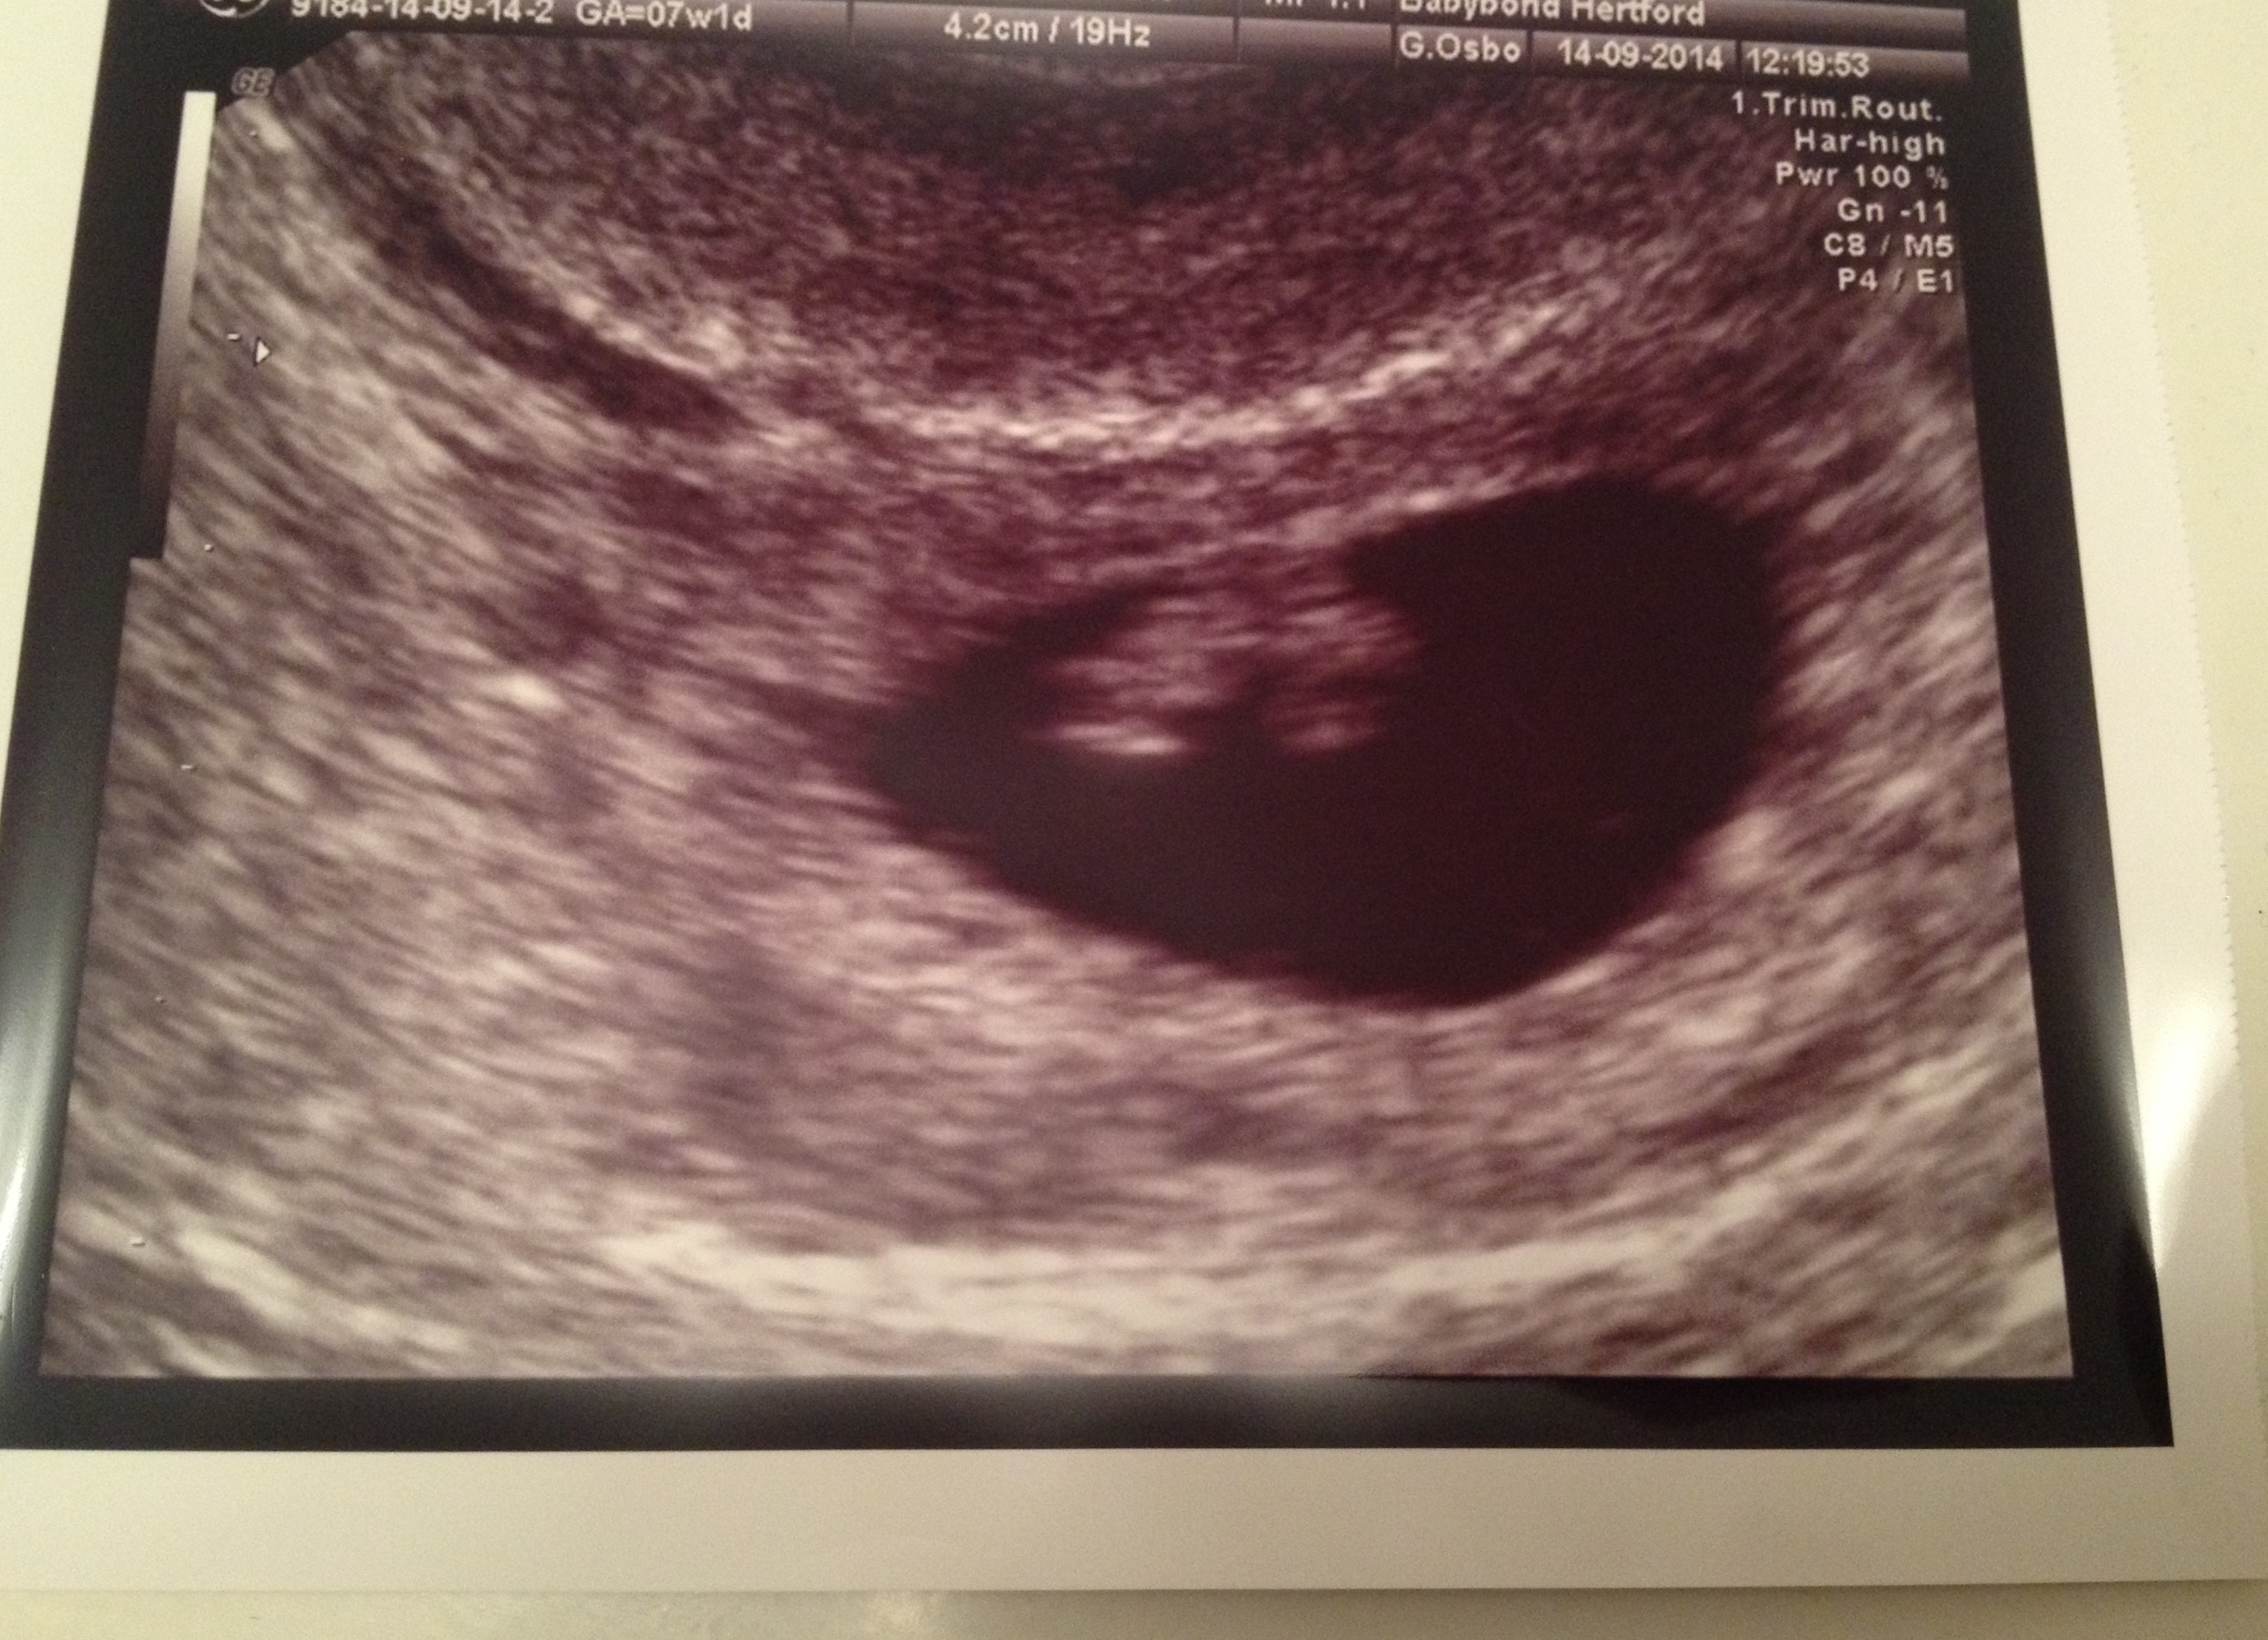

what do you think i will have? its transvaginal u/s

If this U/S was done transvaginal.

Then i would Guess Girl!

My second daughter ultrasound was exactly like yours.

based on the theory it would be a girl. But remember dont take it as 100%